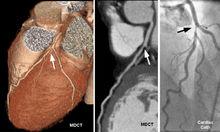

診斷和鑑別診斷:診斷主要根據靜息、動態或負荷試驗的心電圖檢查,和(或)放射性核素心肌顯像,發現患者有心肌缺血的改變,而無其他原因,又有動脈粥樣硬化的危險因素。進行選擇性冠狀動脈造影檢查可確立診斷。